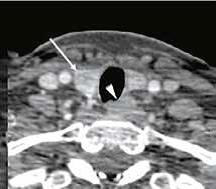

С 2020 по 2022 годы: «Изучение механизмов повреждения сердечно-сосудистой системы при гипо- и гиперпаратиреозе с целью разработки комплексного персонифицированного подхода обследования и лечения». В рамках данной работы проведен анализ встречаемости сердечно-сосудистой патологии и ее спектра у больных первичным гиперпаратиреозом. Установлены особенности ремоделирования сердца и сосудов в условиях гиперкальциемии и изменения после паратиреоидэктомии. Внедрено использование метода ПЭТ/ КТ с 11С-метионином и холином для диагностики эктопированных и множественных аденом околощитовидных желез. Установлено,что чувствительность и специфичность ПЭТ-КТ при диагностикеаденом околощитовидных желез выше, чем у стандартных методов исследования (МСКТ, сцинтиграфия и УЗИ). Дополнительно наблюдение за больными гипопаратиреозом (гипоПТ) показало, что качество жизни пациентов значимо снижено как со стороны физического, так и со стороны ментального здоровья. После коррекции терапии показатели качества жизни значимо вырастают. Проведен анализ встречаемости ССЗ у больных гипоПТ. Было показано, что у больных хирургическим гипоПТ преобладает артериальная гипертензия, а у больных нехирургическим гипоПТ преобладают нарушения ритма и проводимости.

| Аденома правой нижней околощитовидной железы и интратиреоидное расположение аденомы левой нижней околощитовидной железы по данным ПЭТ-КТ с 11С-МЕТ. | |